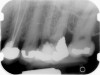

Clinical procedure: If apical bone loss is present (Figure 1) a collagen/gelatin sponge (eg, Gelfoam®, Pfizer Inc., www.pfizer.com) can be placed apically so that the MTA can be delivered to the desired working length. (Any other surgical resorbable sponge would also work, such as OraPlug® [Salvin Dental Specialties, www.salvin.com], Surgifoam® [Midwest Dental, www.mwdental.com], or Surgispon® [Aegis Lifesciences, www.surgispon.com]). This is done by taking a small piece (2 mm x 2 mm) of the resorbable sponge and pushing it down to and through the root apex with an endodontic file. Once this is done, MTA is packed down the canal with a custom-fitted cone. The clinician can use a rubber stopper on the gutta-percha cone to know the exact length of MTA placed in the apical third (Figure 2). Once the apical third is sealed with 3 mm to 5 mm of MTA, the remaining coronal canal space can be back-filled using a warm gutta-percha technique (Figure 3).

Fig 1. Preoperative radiograph showing apical bone loss.

Figure 1